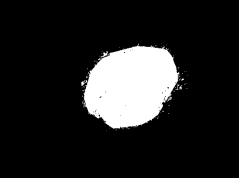

Skin lesion segmentation is one of the crucial steps for an efficient non-invasive computer-aided early diagnosis of melanoma. This paper investigates how color information, besides saliency, can be used to determine the pigmented lesion region automatically. Unlike most existing segmentation methods using only the saliency in order to discriminate against the skin lesion from the surrounding regions, we propose a novel method employing a binarization process coupled with new perceptual criteria, inspired by the human visual perception, related to the properties of saliency and color of the input image data distribution. As a means of refining the accuracy of the proposed method, the segmentation step is preceded by a pre-processing aimed at reducing the computation burden, removing artifacts, and improving contrast. We have assessed the method on two public databases, including 1497 dermoscopic images. We have also compared its performance with classical and recent saliency-based methods designed explicitly for dermoscopic images. The qualitative and quantitative evaluation indicates that the proposed method is promising since it produces an accurate skin lesion segmentation and performs satisfactorily compared to other existing saliency-based segmentation methods.